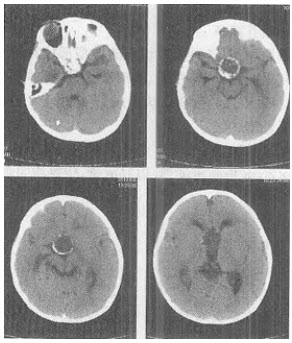

患儿,男,5岁,CT平扫图像如下,最可能的诊断是()

A、垂体瘤

B、透明隔囊肿

C、颅咽管瘤

D、蛛网膜囊肿

E、Rathke裂囊肿

正确答案:

C